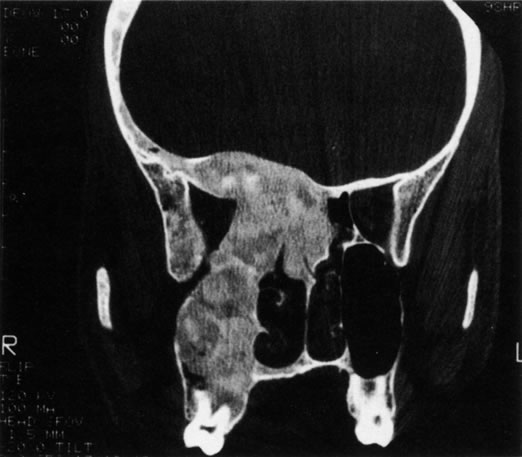

Many congenital cystic structures may arise from or involve the orbit. Some cystic structures, such as meningoencephaloceles or mucoceles, result from defects in the bony sutures of the cranial skeleton, allowing herniation of adjacent structures into the orbit. Other cystic structures, such as dermoid cysts, teratomas, and epithelial cysts, result from developmental anomalies of the orbital soft tissues. Most isolated orbital cysts have a subtle clinical presentation at birth, although some may present with extreme proptosis (Fig. 3). Ultrasonography can aid in the prenatal detection and monitoring of large orbital cysts.5